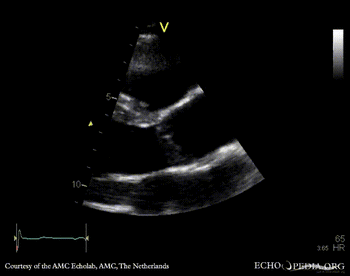

E00339.gif E00340.gif

PLAX: thickend aortic valve PLAX: Color Doppler, moderate aortic regurgitation